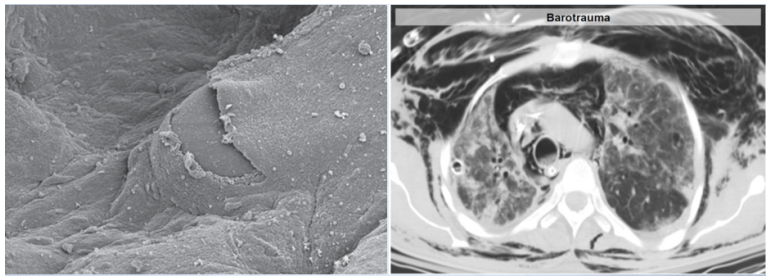

1. 导致呼吸机相关肺损伤(VILI)

ARDS患者行机械通气时,相当于在原有肺过度膨胀的基础上增加了正压通气,由此加重了肺膨胀,肺可能被“吹爆”,并且可能导致气胸、纵隔气肿、皮下气肿甚至梗阻性休克,同时肺泡表面损伤也非常严重(图3)

图片

图3  ARDS患者肺组织的电子显微镜照片

图源:Crit Care Med, 2002, 30(10):2368-2370.